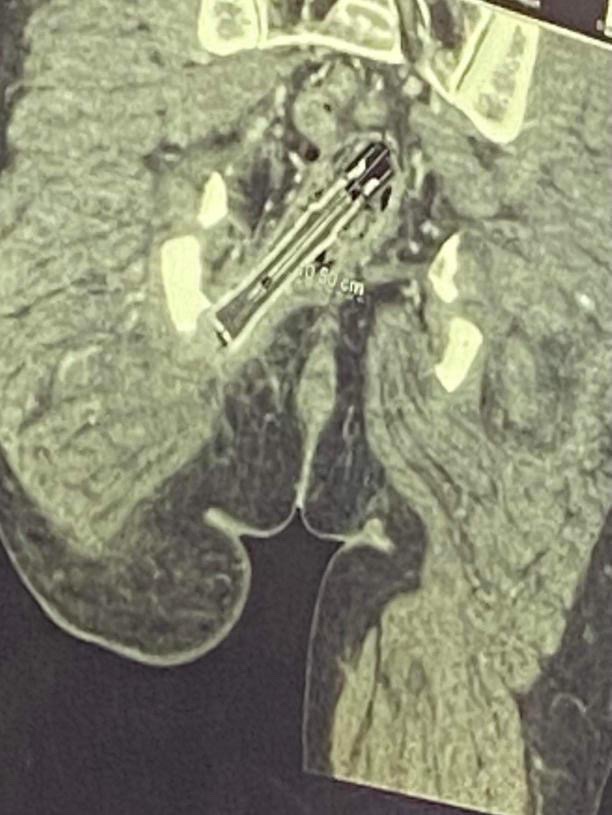

Date Vape Gallery Date Vape By Nicole Angemi|2025-10-02T11:08:26-04:00November 6th, 2021|The Gross Room, FREAK ACCIDENT, Foreign Bodies, Sex Injuries| Read More 20